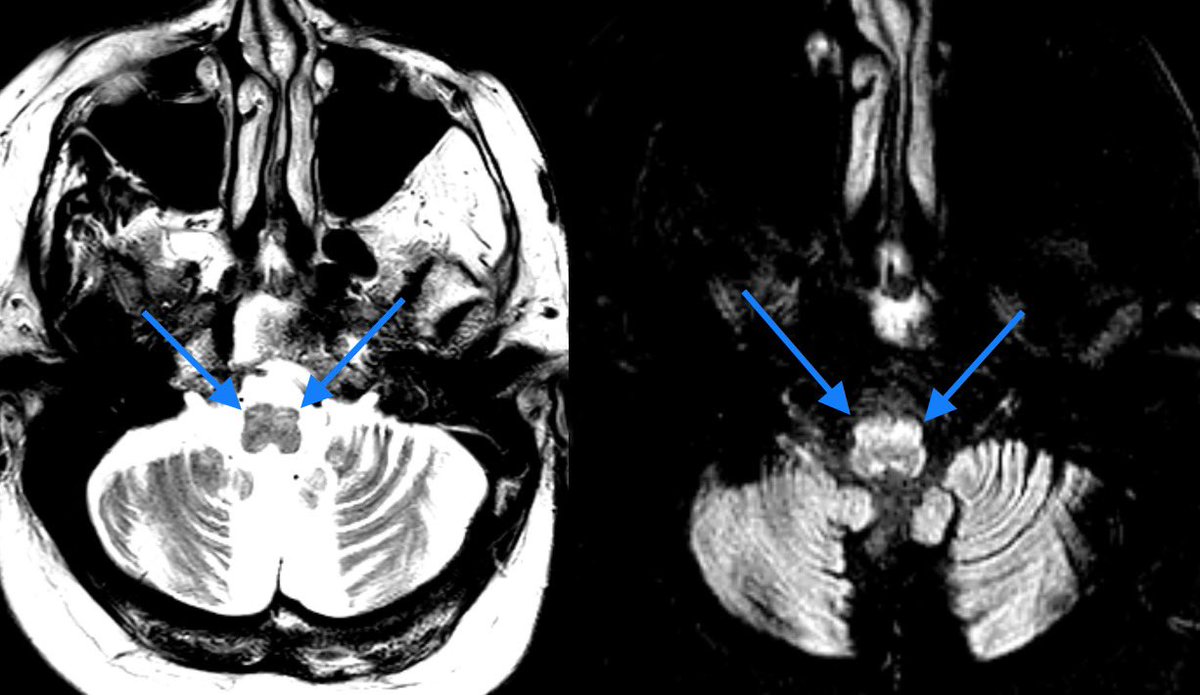

Lesions that disrupt the triangle of Guillain and Mollaret (neural pathway connecting the red nucleus, inferior olivary nucleus, and contralateral dentate nucleus) can result in swollen inferior olivary nuclei

Imaging: T2/FLAIR bright and swollen inferior olivary nuclei w/o enhancement

š” Can be unilateral or bilateral if a lesions disrupts both pathways of the GMT